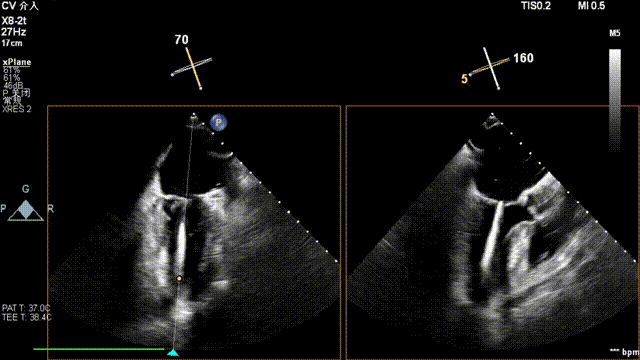

全麻后,二尖瓣夹合器系统在心前区的肋间切开3-4CM小切口,暴露心脏的心尖位置,送系统送入左心房,顺利到达病变二尖瓣区域。在经食道超声辅助下,术者通过反复评估二尖瓣反流位置、抓捕位置、反流程度,首先在2偏3区位置处于二尖瓣闭合线垂直进行巧妙夹合。在2区靠近3区位置处植入了1枚ValveClamp®MVC-IIf夹,最终评估评估反流降至轻度,平均跨瓣压差降至2mmHg,手术取得圆满成功。

术中超声(关键步骤)